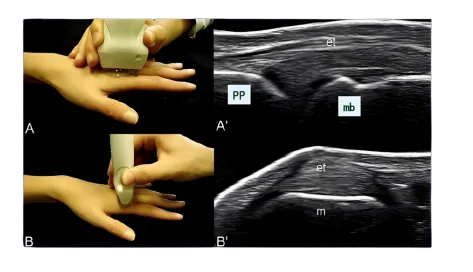

什么是肌骨超声

是一项利用高频超声波对肌肉、骨骼及周围软组织进行实时、动态成像的先进检查技术。它就像为您身体内部进行的 “高清现场直播”。医生通过探头在皮肤表面滑动,可以清晰观察到皮下的肌肉、肌腱、韧带、关节囊、神经的细微结构与动态情况。

实时动态:活动肢体同步检查,比静态更精准;